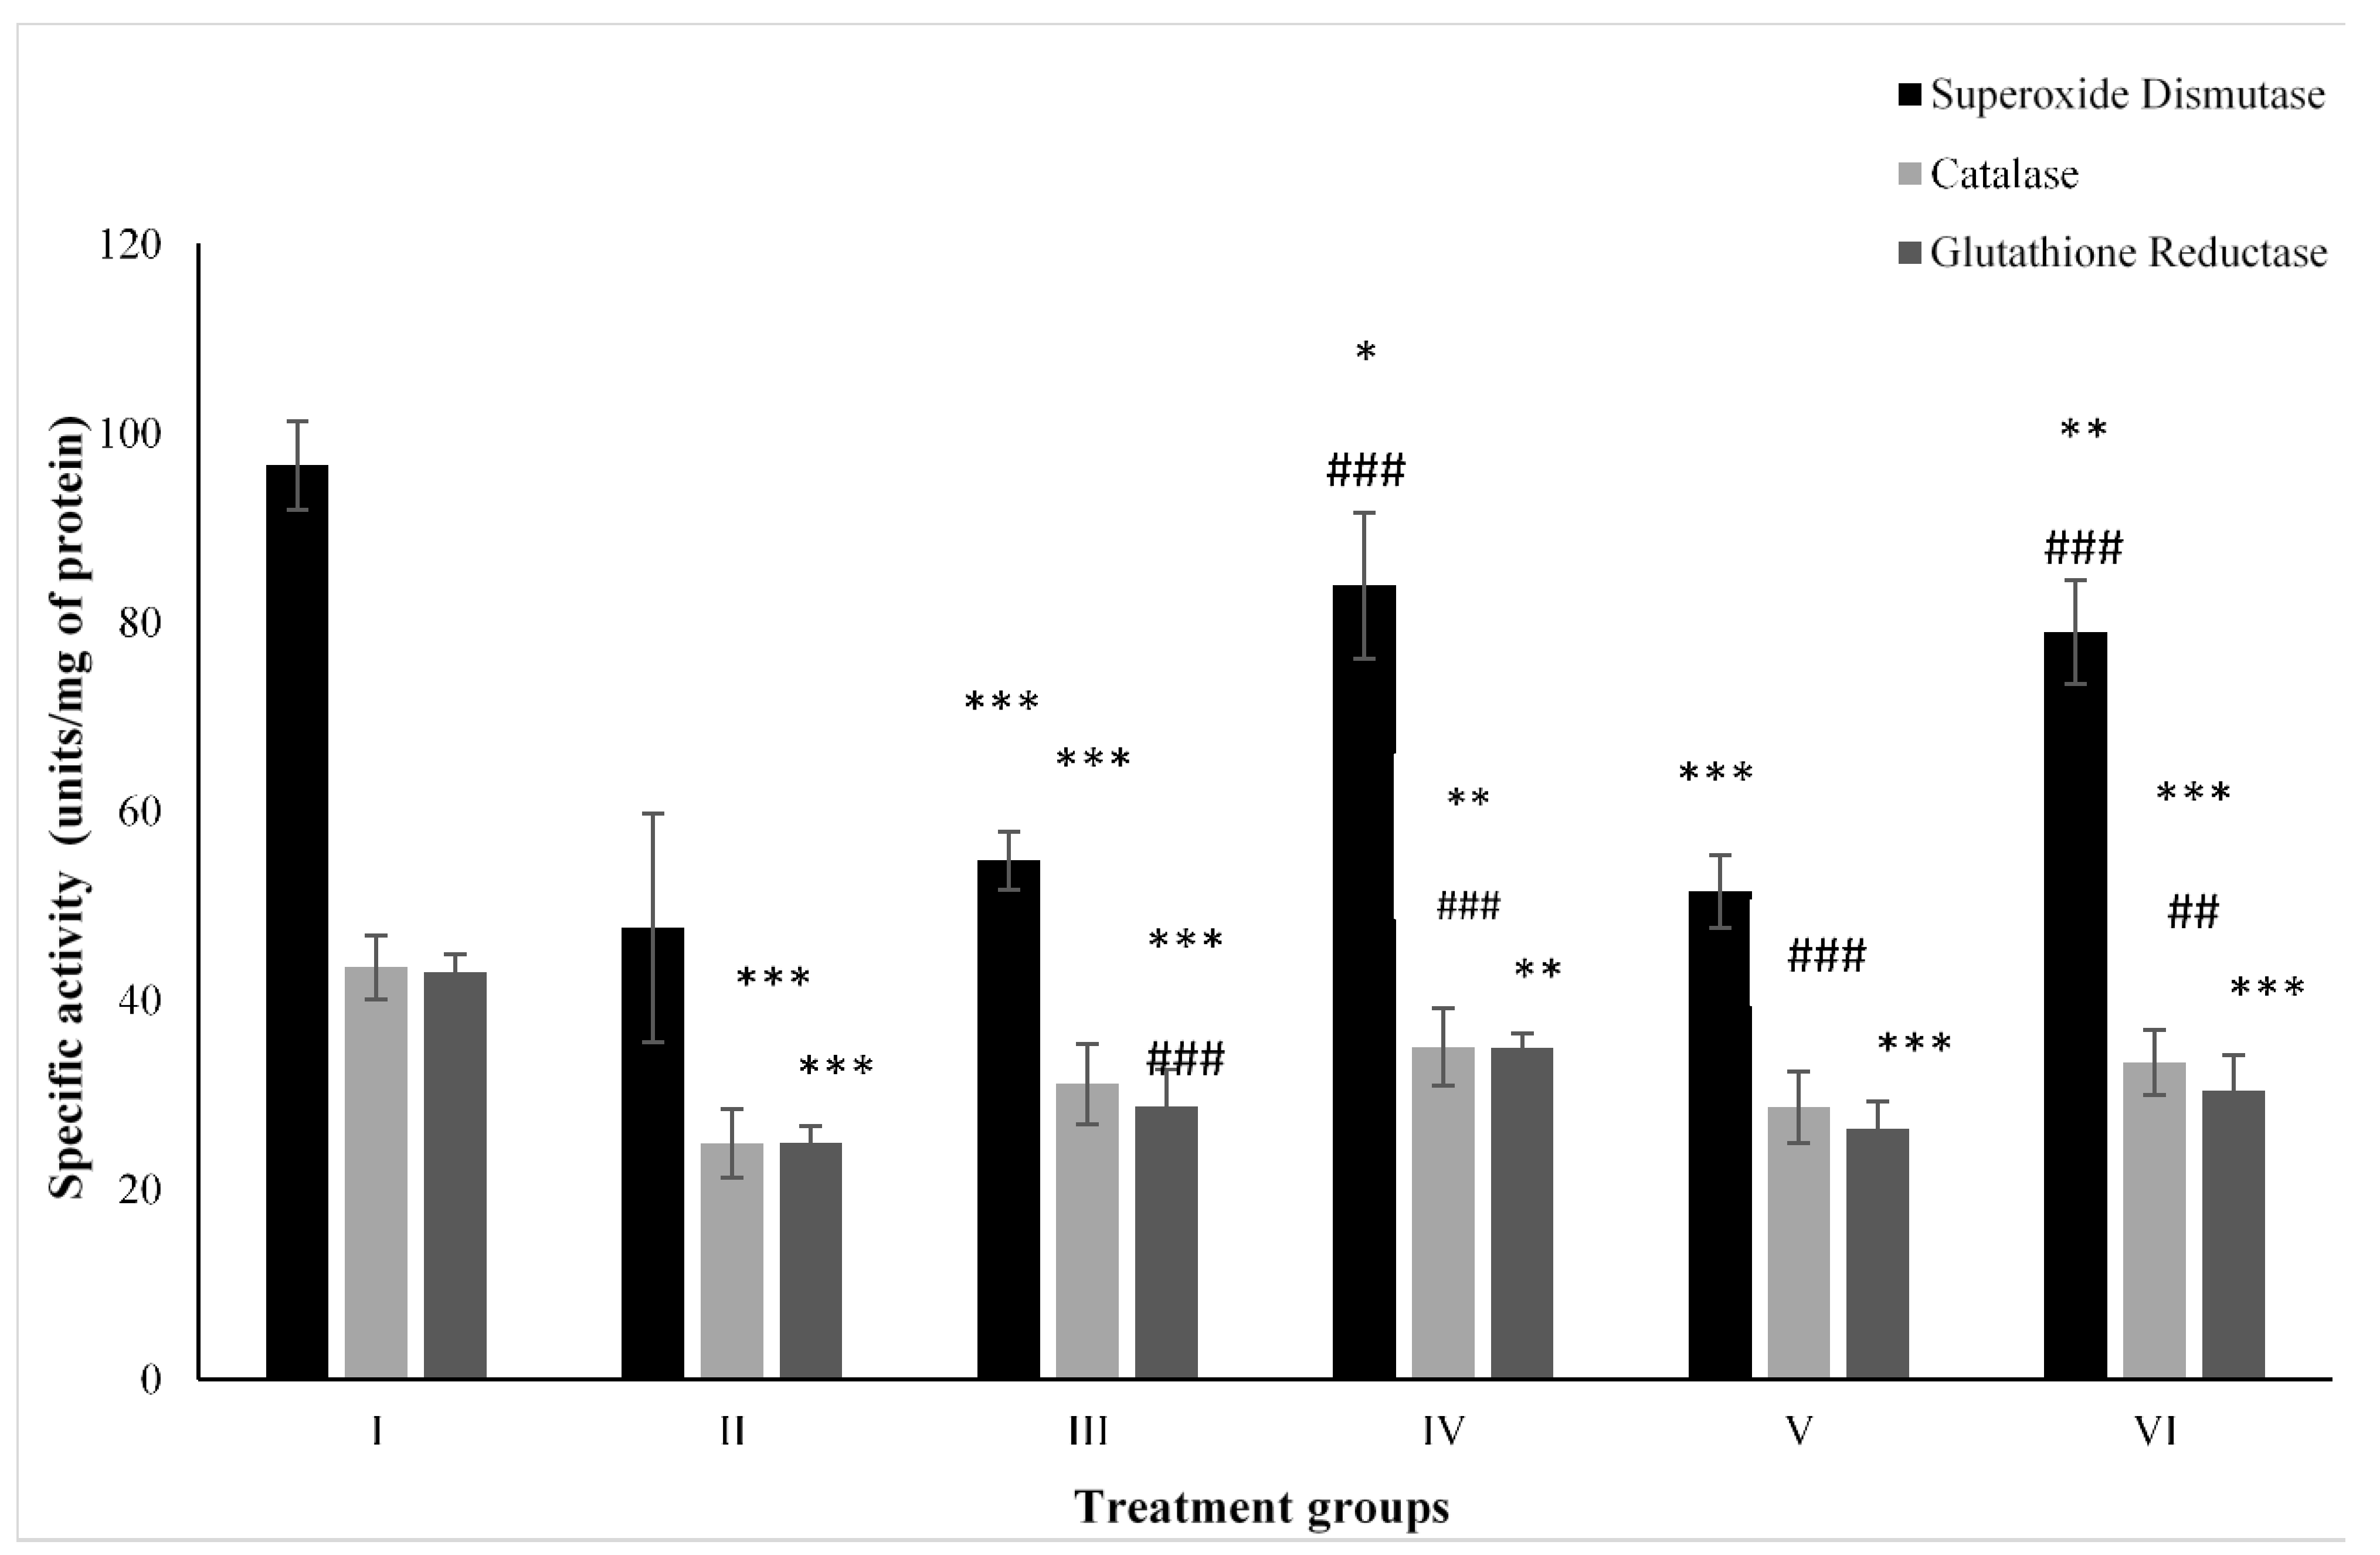

2.4. Effect on Antioxidant Parameters

2.4.1. CAT

2.4.2. SOD

2.4.3. GR